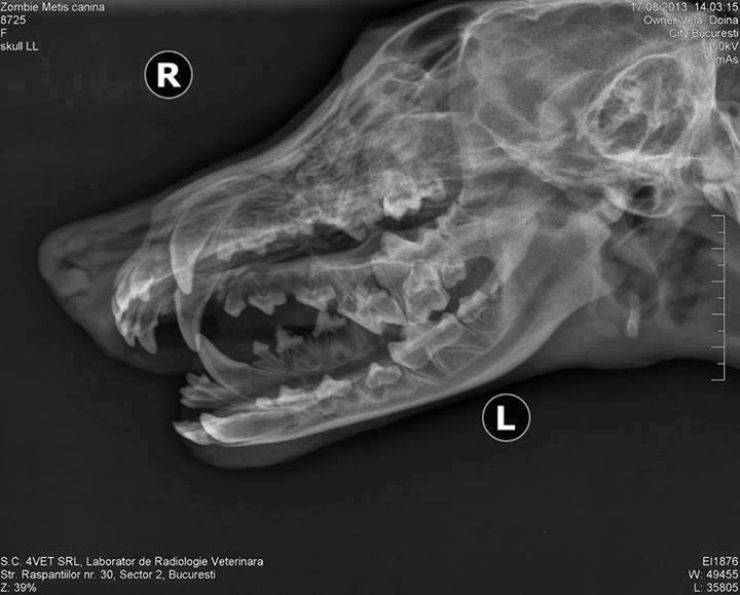

Lina è stata trovata mentre vagava per le strade di Bucarest, in Romania, in gravi condizioni: la cucciola aveva la mascella rotta.

Secondo quanto dichiarato da Hilary Anderson, volontaria di Barking Mad Dog Rescue: “Lina è stata trovata per la prima volta in un cantiere con la mascella fracassata. E senza dubbio l’atto è stato compiuto deliberatamente.”